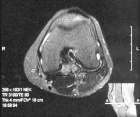

26 year old female with pain and swelling in the right knee for two years

Zoom image: Radiological image Radiological image.